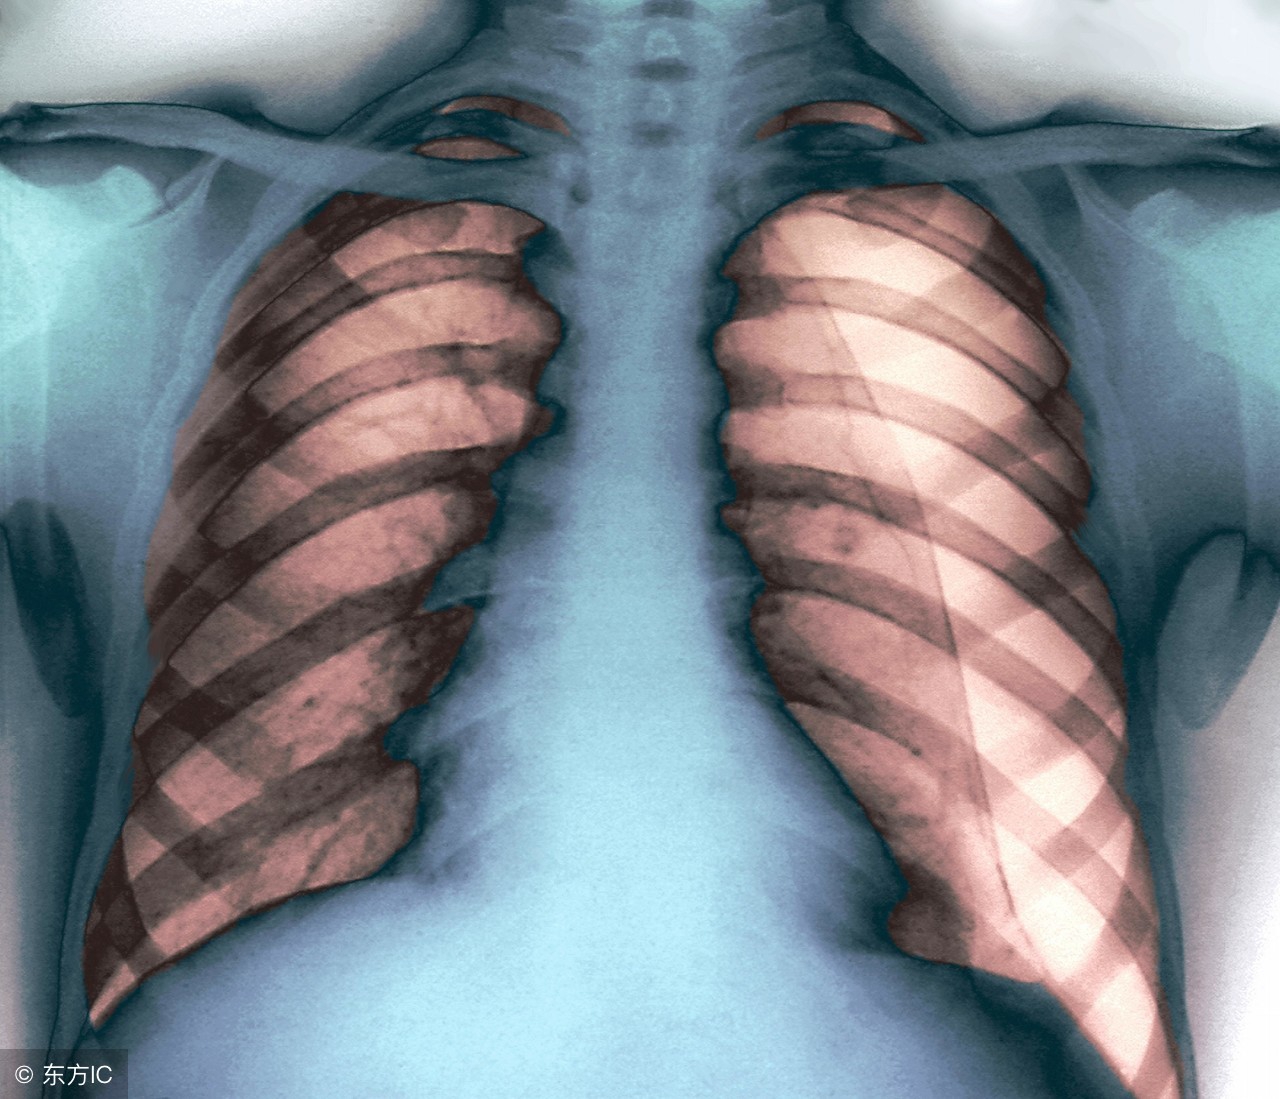

肺大疱作为临床上一种并不罕见的肺部疾病,如果患者没有足够的重视,给患者机体健康带来的危害往往是比较大的。但是在实际生活中,很多人对于该疾病所具有的了解和认识还是比较少的。那么,对于这一疾病,究竟应当要怎样进行治疗好呢?得了肺大疱的患者可能会疑惑,该疾病不治疗的话,能不能自愈呢?